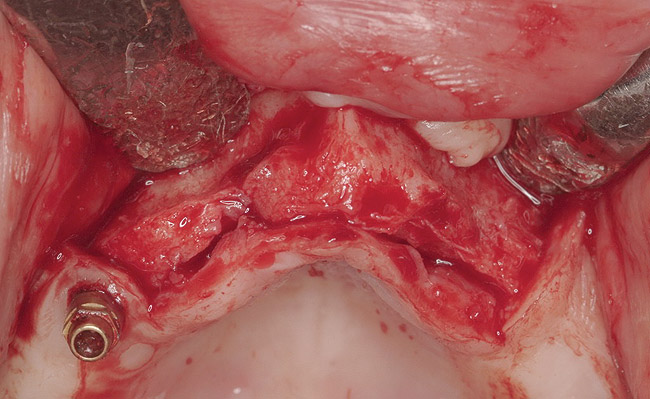

Clinical and radiographic evaluation revealed significant alveolar ridge resorption and maxillary sinus pneumatization. The patient was informed that to achieve her goal of wearing a fixed prosthesis, she would require bilateral sinus grafts and anterior ridge augmentation, which she agreed to undergo. Following augmentation of her right and left maxillary sinuses, she presented for reconstruction of her severely atrophic anterior region. Following reflection of a full-thickness flap, severe bone loss was evident, especially in the right canine–lateral incisor region (Figure 15). Following decortication of the buccal cortex with a #2 round bur, a composite graft consisting of 0.8 mg of rhBMP-2/ACS + 0.7 cc of FDBA was adapted to the facial surface of the ridge from the maxillary right to the left canine regions. A bioresorbable PLGA mesh was then contoured and affixed with two PLGA screws 4 mm in length and 1.5 mm in diameter. Additional particulate FDBA graft was then placed under the mesh to obturate the entire space between the bony surface of the ridge and the mesh (Figure 16). A non-cross-linked collagen tape (CollaTape®, Zimmer Dental, www.zimmerdental.com) was applied over the mesh for containment of the particulate bone graft, followed by periosteal-releasing incisions and tension-free primary closure with monofilament polytetrafluoroethylene (PTFE) sutures (Figure 17).

Figure 15  Full-thickness flap revealed severe bone loss, particularly in right canine–lateral incisor region.

Figure 15

Figure 16  Additional particulate FDBA graft placed under mesh.

Figure 16